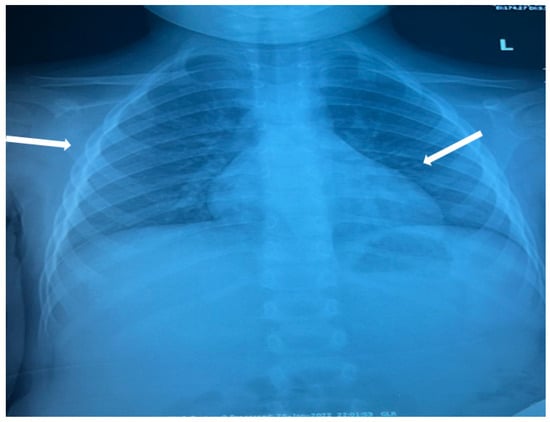

The patient was hospitalized in the Pediatric Clinic I for 3 weeks, being closely monitored (seriated clinical exam, laboratory tests, and echocardiography). The patient’s evolution gradually became favorable, and he was discharged with the recommendation to continue antiplatelet therapy and low-dose oral steroids. However, 4 days after discharge, the patient presented to the Emergency Department with altered general condition, respiratory distress, and fatigue. Laboratory tests revealed leukocytosis (27.720 × 103/μL), with neutrophilia (22.970 × 103/μL), thrombocytosis (491 × 103/μL), monocytosis (2.180 × 103/μL), and elevated inflammatory markers (CRP > 180 mg/L, ESR 43 mm/h), while urine analysis and cardiac enzymes were within normal limits. In the emergency department, a chest X-ray was performed which pointed out diffuse peribronchovascular infiltrates and inferior interclavicular hilar infiltrates (Figure 1). Given the influenced general condition and the presence of respiratory failure (oxygen saturation of 90%), along with the findings of the chest X-ray, we decided also to perform pulmonary computed tomography (CT), which identified ground-glass opacities with subpleural disposition adjacent to the mediastinum, in the upper lobes at the apical and posterior segments of the right lung, and at the apicoposterior segment of the left lung. Additionally, in the lower pulmonary lobes, opacities were observed in the bilateral posterior segments, left anteromedial, and right medial segments, indicative of possible pulmonary hypertension/incipient pulmonary edema/acute respiratory distress syndrome (ARDS) (Figure 2 and Figure 3). Pulmonary hypertension and pulmonary edema were ruled out based on clinical findings, cardiac examination, and normal cardiac enzymes. Based on all these findings, we considered pneumonia in the context of immunosuppression and we performed several tests to identify the possible etiology, finding elevated positive anti-CMV IgM antibodies and increased IgG antibodies of CMV (967.9 U/mL), which were confirmed by subsequent repeated tests. Additionally, we found evidence of hepatocellular injury (ALT: 166 U/L; AST: 60.7 U/L) prompting intravenous hepatoprotective treatment and initiation of an unspecified immunomodulatory agent, inosine acedoben dimepranol, orally, at a dose of 50 mg/kg body weight per day. This approach was chosen due to limitations in specific antiviral therapy for the pediatric population.

Figure 2. Ground-glass opacities with subpleural disposition adjacent to the mediastinum, in the upper lobes at the apical and posterior segments of the right lung, and at the apicoposterior segment of the lung (white arrows).